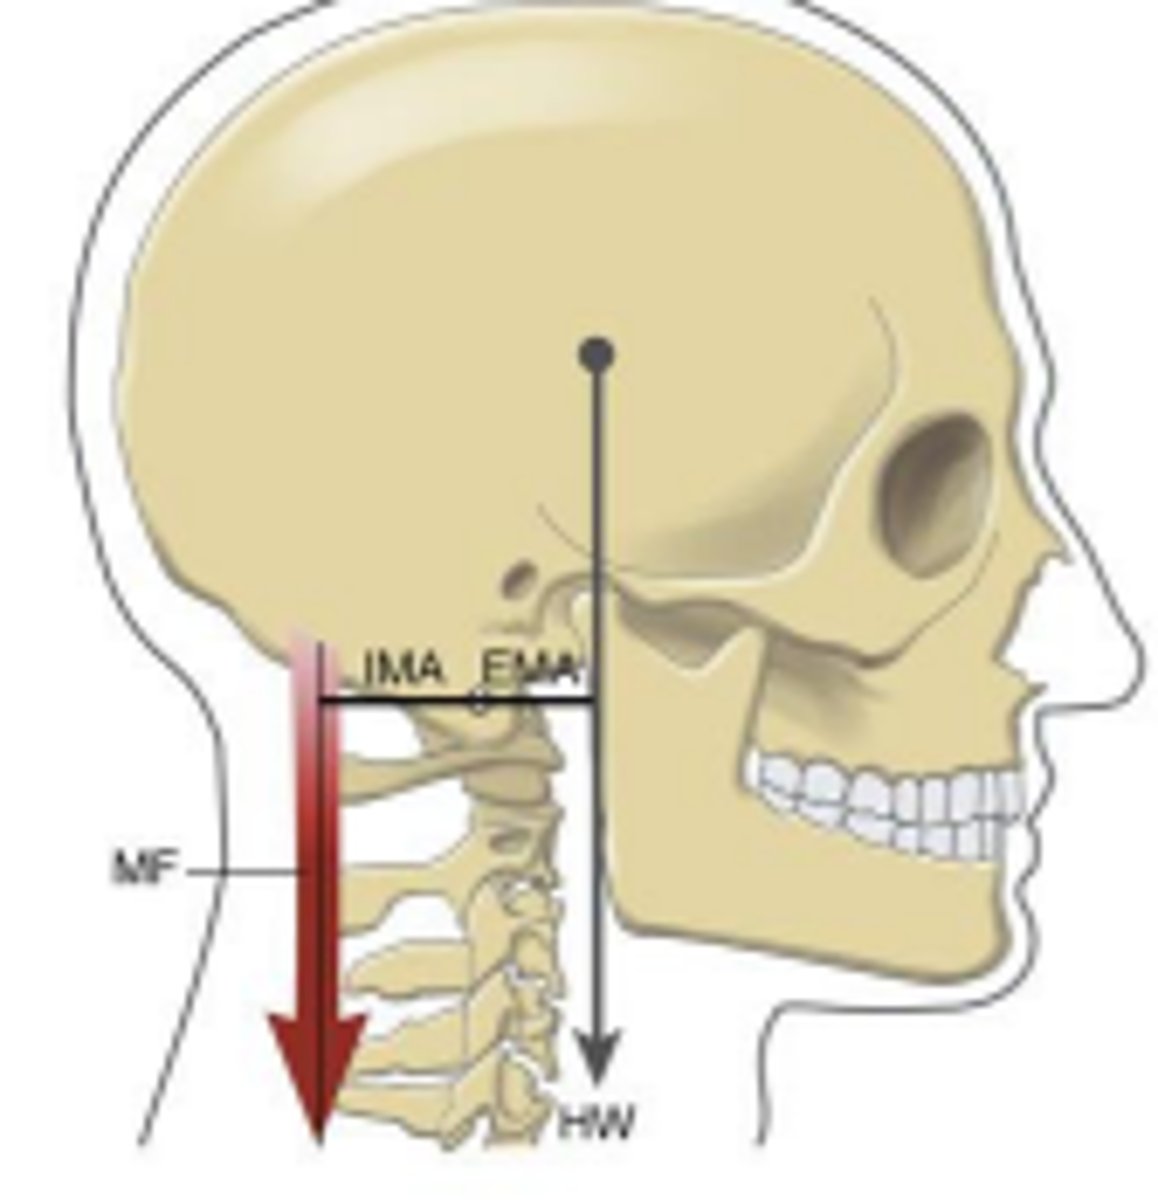

Which lever does this picture represent?

What does the red arrow represent?